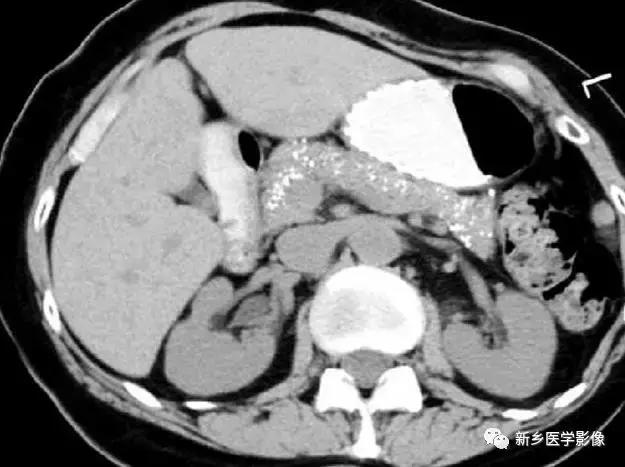

慢性胰腺炎

主要表现为胰腺体积缩小,钙化,有时候假性囊肿囊壁也可钙化。

棘球蚴病

肾上腺囊性病变

主要包括合并钙化的感染性病变及肿瘤性病变,如: 肾上腺囊肿,肾上腺癌,嗜铬细胞瘤